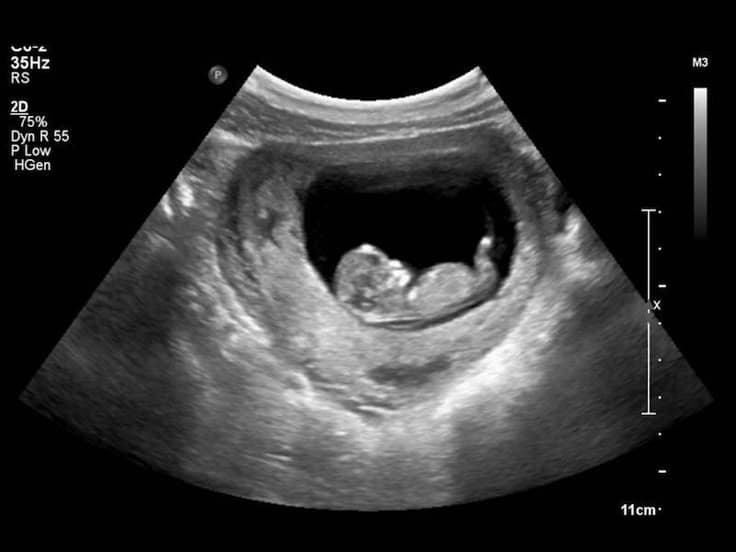

The first trimester which lies between conception to about twelve weeks was marked by nausea, vomiting, mood swings, food cravings, breast changes, tiredness and frequent urination. The frequent urination in particular disgusted her most, but she had to brace herself and put up with it. In her second trimester, the morning sickness eased and she had some energy in her, getting used to the physical and emotional changes that proved inevitable in the path of pregnancy. Her stomach was almost visible by now, it couldn’t be hidden any more. The whole world knew. She remained unbothered, giving a deaf ear to society’ s uncalled for judgements. It was at this period of time that she felt the first movements of her child, it was miraculous, it strengthened her.

The third trimester marked the peak of her pregnancy as she anticipated welcoming her unborn into the world. She felt the kicks and jabs in her stomach, and wondered what a lively child her unborn would grow into. The unwanted child. She connected with her child, sensing when he was awake or asleep. Then came the labour pains, marked by intense rhythmic contractions of the uterus. She was rushed into the nearby dispensary, unable to contain the foreign pain that held her captive. The deep cramping started from her lower back and radiated to her abdomen, growing stronger and frequent. She was taken into the delivery room, hours upon arrival due to lack of space in the small crumpled dispensary that served more than it barely could.